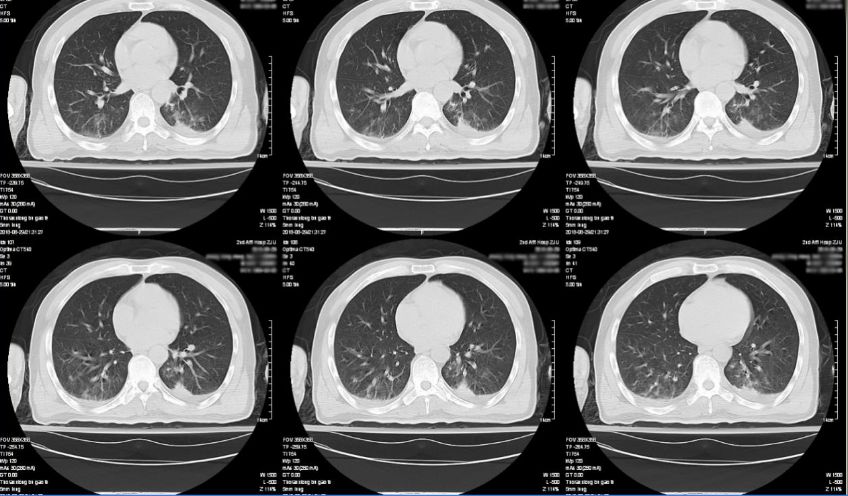

入院后第14日,患者意识水平下降,查体:昏睡状态,瞳孔左侧直径2mm,右侧直径3mm,对光反射迟钝,舌根后坠,肢端青紫,氧饱和度下降至80%,紧急联系气管插管转脑重症监护室。急诊头胸部CT检查,提示左额出现新发病灶(图7),肺部感染较前加重(图8)。

图8. 入院后第14天,胸部CT提示患者肺部感染较前加重。